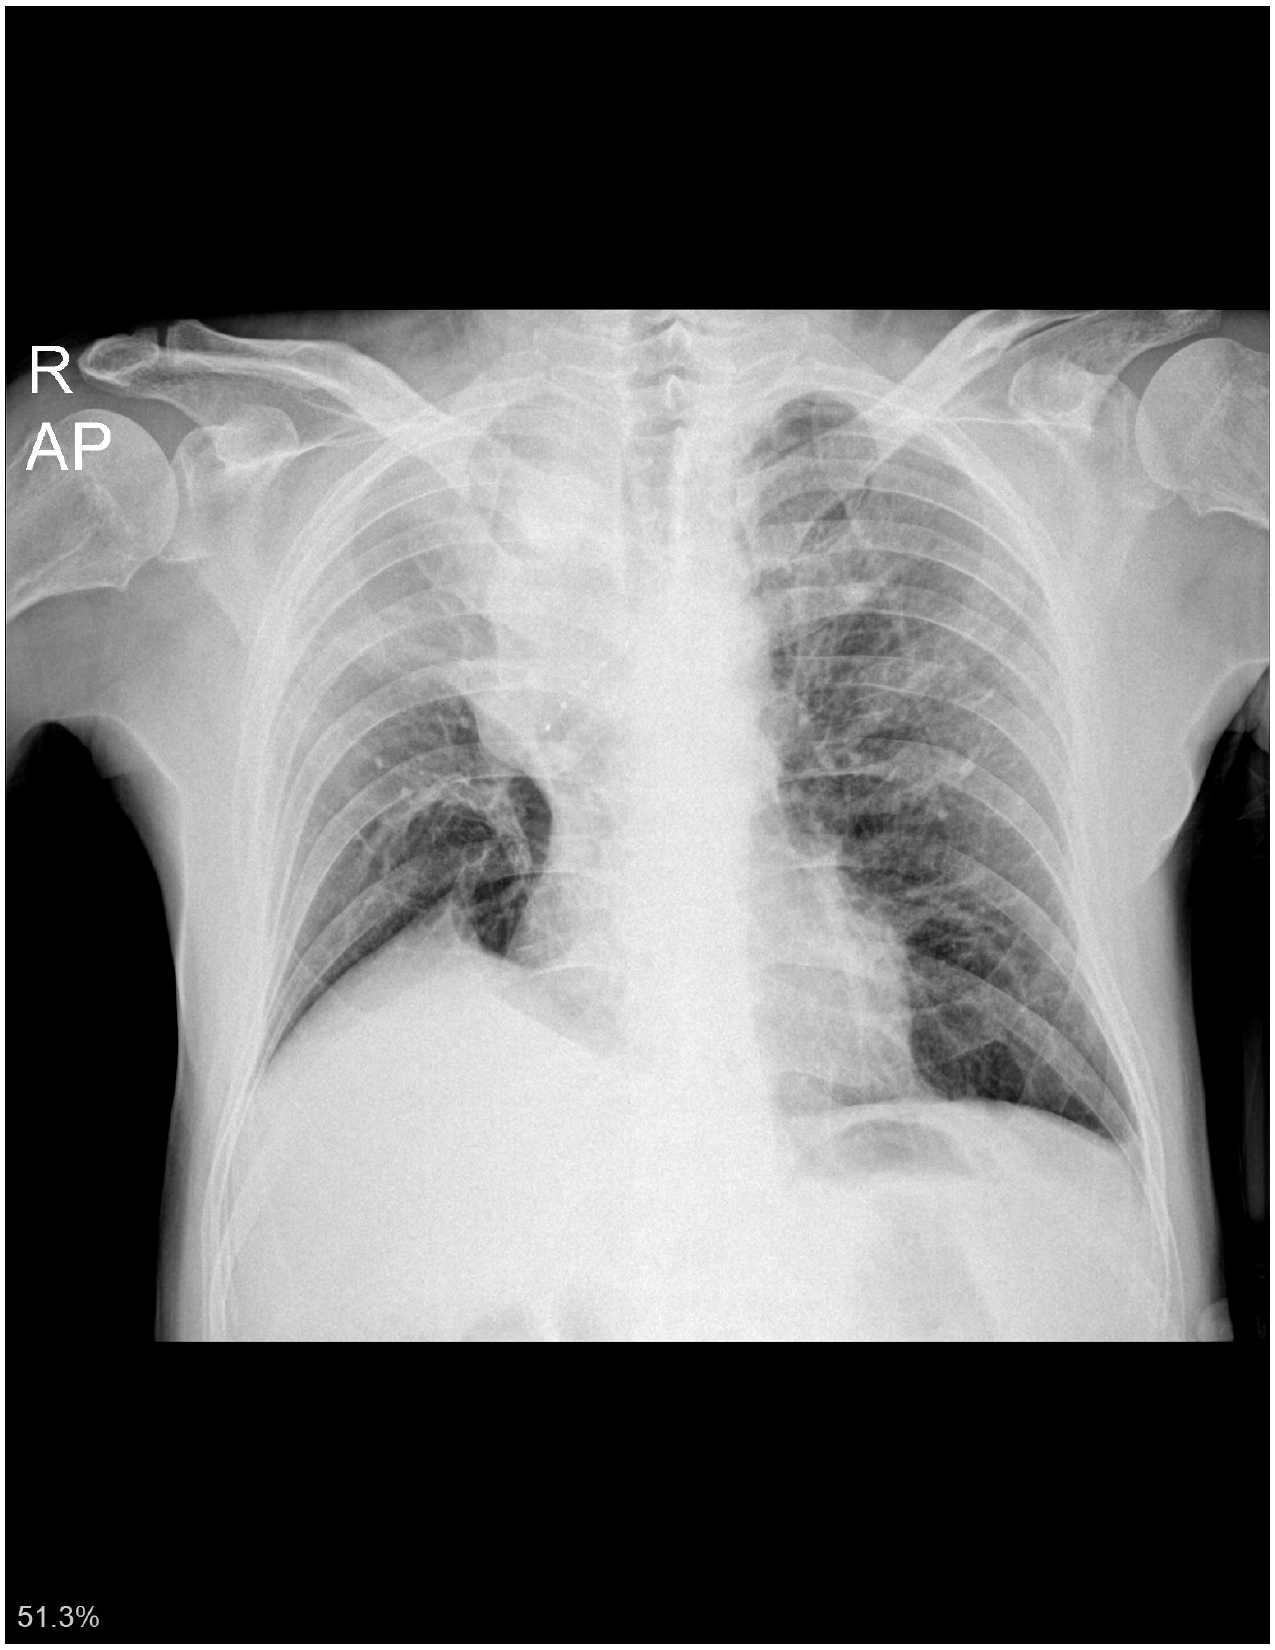

- CXR სტენტირების მეორე დღეს

- გულმკერდის CXR სტენტირების მეათე დღეს